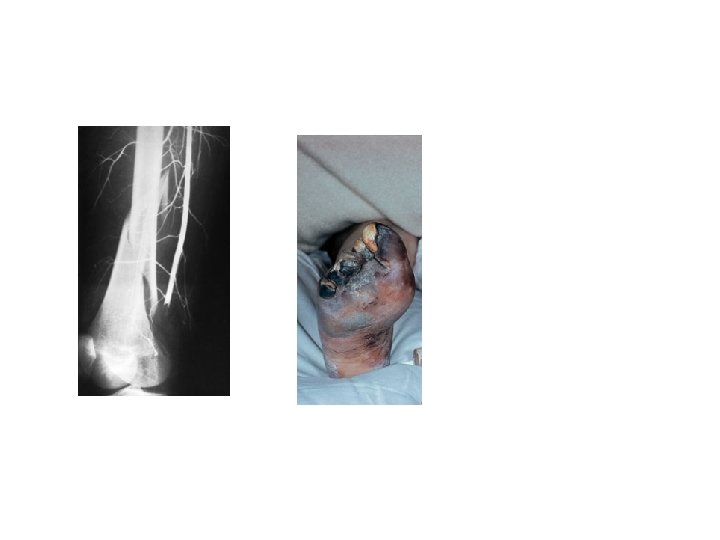

2 -VASCULAR INJURY The fractures most often associated with damage to a major artery are those around the knee and elbow, and those of the humeral and femoral shafts. The artery may be cut, torn, compressed or contused, either by the initial injury or subsequently by jagged bone fragments. The effects vary from transient diminution of blood flow to profound ischaemia, tissue death and peripheral gangrene.

• Clinical features The patient may complain of paraesthesia or numbnessin the toes or the fingers. The injured limb is cold and pale, or slightly cyanosed, and the pulse is weak or absent. X-rays will probably show one of the ‘highrisk’fractures listed above. If a vascular injury is suspected an angiogram should be performed immediately; if it is positive, emergency treatment must be started without further delay. • Treatment All bandages and splints should be removed. The fracture is re-x-rayed and, if the position of the bones suggests that the artery is being compressed or kinked, prompt reduction is necessary. The circulation is then reassessed repeatedly over the next half hour. If there is no improvement, the vessels must be explored by operation preferably with the benefit of preoperative or peroperative angiography. A cut vessel can be sutured, or a segment may be replaced by a vein graft; if it is thrombosed, endarterectomy may restore the blood flow. If vessel repair is undertaken, stable fixation is a must and where it is practicable, the fracture should be fixed internally.